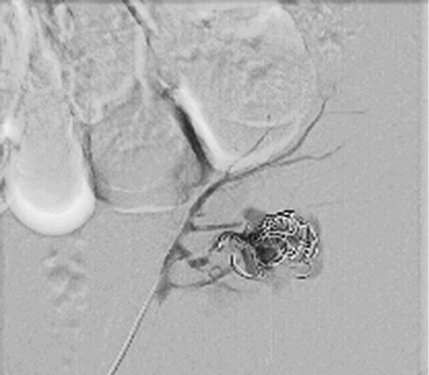

Pseudoaneurysm was embolized with two 8 mm x 20 cm coils, an additional coil of 12 mm x 30 cm (Figure 5).

Control angiography with contrast was performed. Pseudoaneurysm was completely occluded and no longer visible (Figure 6). No extravasation was found.

After embolization, creatinine decreased till 83 µmoL/L and eGFR was 73 mL/min/1.73 m2. Pseudoaneurysm was no longer visible, as well as small segmental branches. Vascularization of renal parenchyma is reduced.

Figure 6. Control angiography after embolization (pseudoaneurysm is no longer visible; small segmental branches in renal parenchyma are not visible)